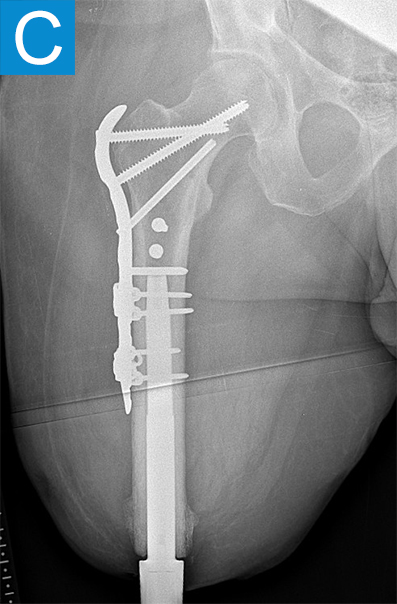

Standing radiographs showed periosteal reaction to the distal femoral isthmus, and given the chronicity of his infections the decision was made to stage the transfemoral amputation and osseointegration implant insertion (Figure 1b). During the amputation, the tibial and peroneal nerves underwent targeted muscle reinnervation to the motor branches of the medial and lateral hamstrings, respectively. Cement mixed with tobramycin and vancomycin was placed in the femoral canal, and the remaining musculature was purse stringed around the residual femur. His proximal cultures were negative, and so no further antibiotic treatment was given. Approximately 8 weeks later, the antibiotic spacer was removed and a press fit femoral osseointegration implant was placed in a percutaneous procedure (Figure 2a). Cultures of the canal remained negative.

Figure 1. Preoperative X-rays show (A) static cement spacer on antibiotic suppression and (B) an antibiotic cement spacer in the residual femur.

Figure 2. Postoperative X-rays shows (A) a femoral osseointegration implant; (B) a subtrochanteric proximal fracture; (C) the femur fracture repaired by open reduction and internal fixation with a proximal locking plate.